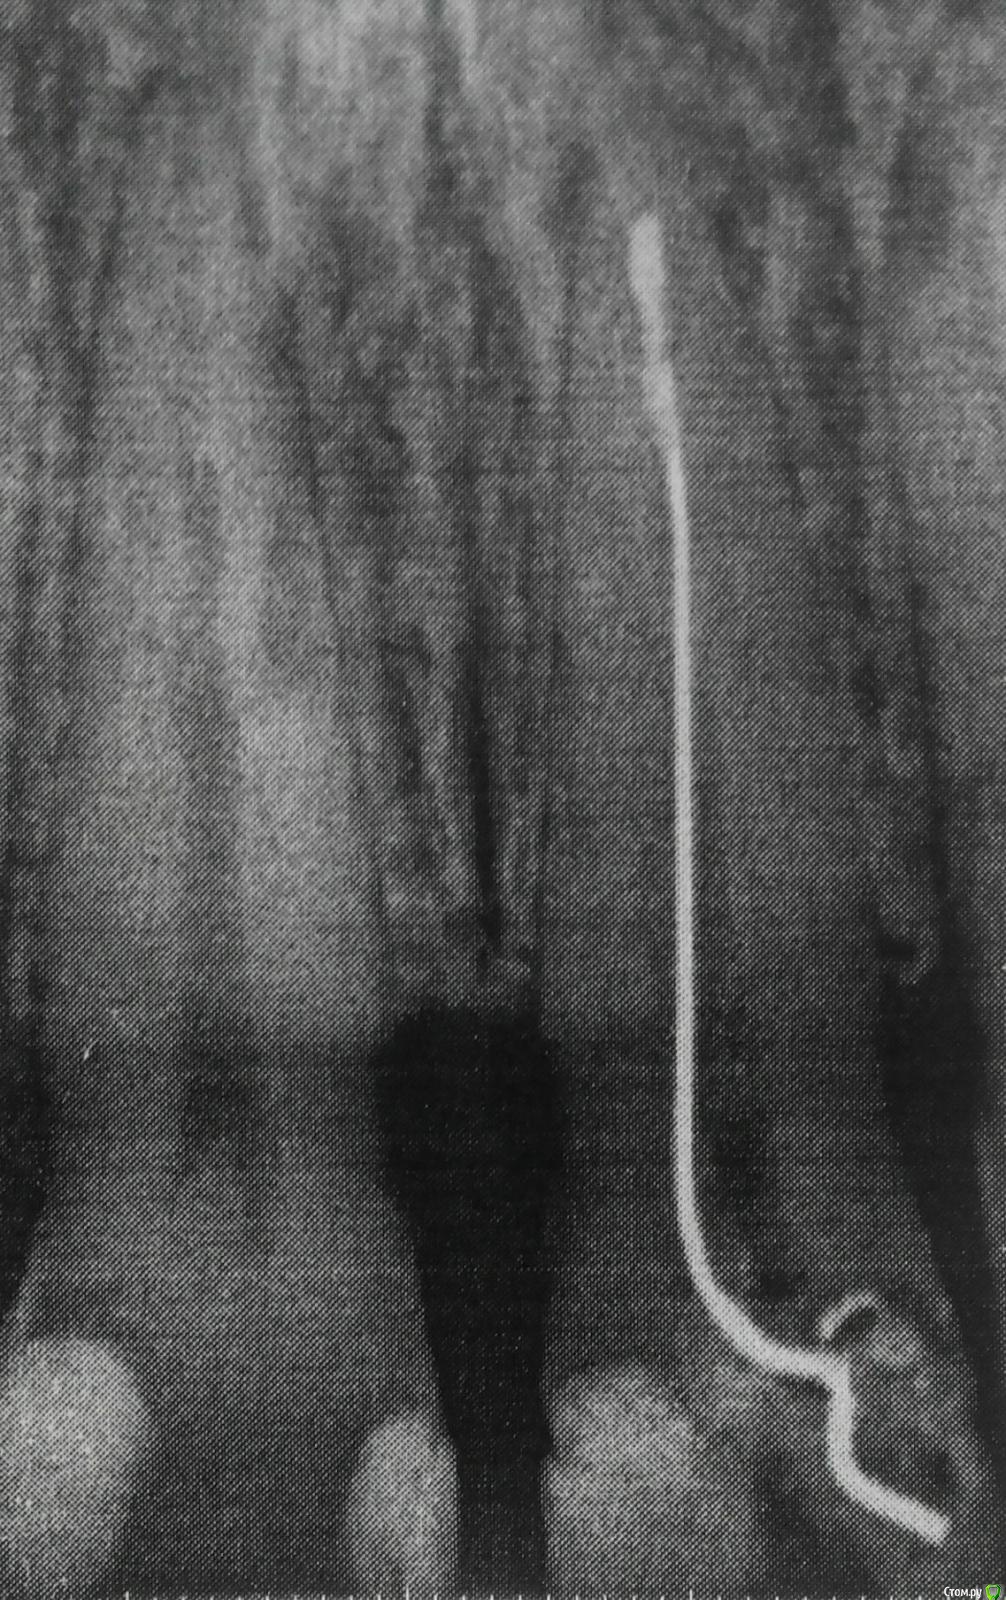

Леголич Опубликовано 24 февраля, 2018 Поделиться Опубликовано 24 февраля, 2018 Доброго времени суток. В 21 зубе 27 лет назад был запломбирован канал при помощи серебряного штифта и какого то не рентген контрастного вещества. Зуб не розовый. Надеюсь найти здесь врача, который имеет реальный опыт прохождения таких каналов и микроскоп. Живу в Москве. Спасибо. Ссылка на комментарий

Леголич Опубликовано 24 февраля, 2018 Автор Поделиться Опубликовано 24 февраля, 2018 Снимок 21 зуба Ссылка на комментарий